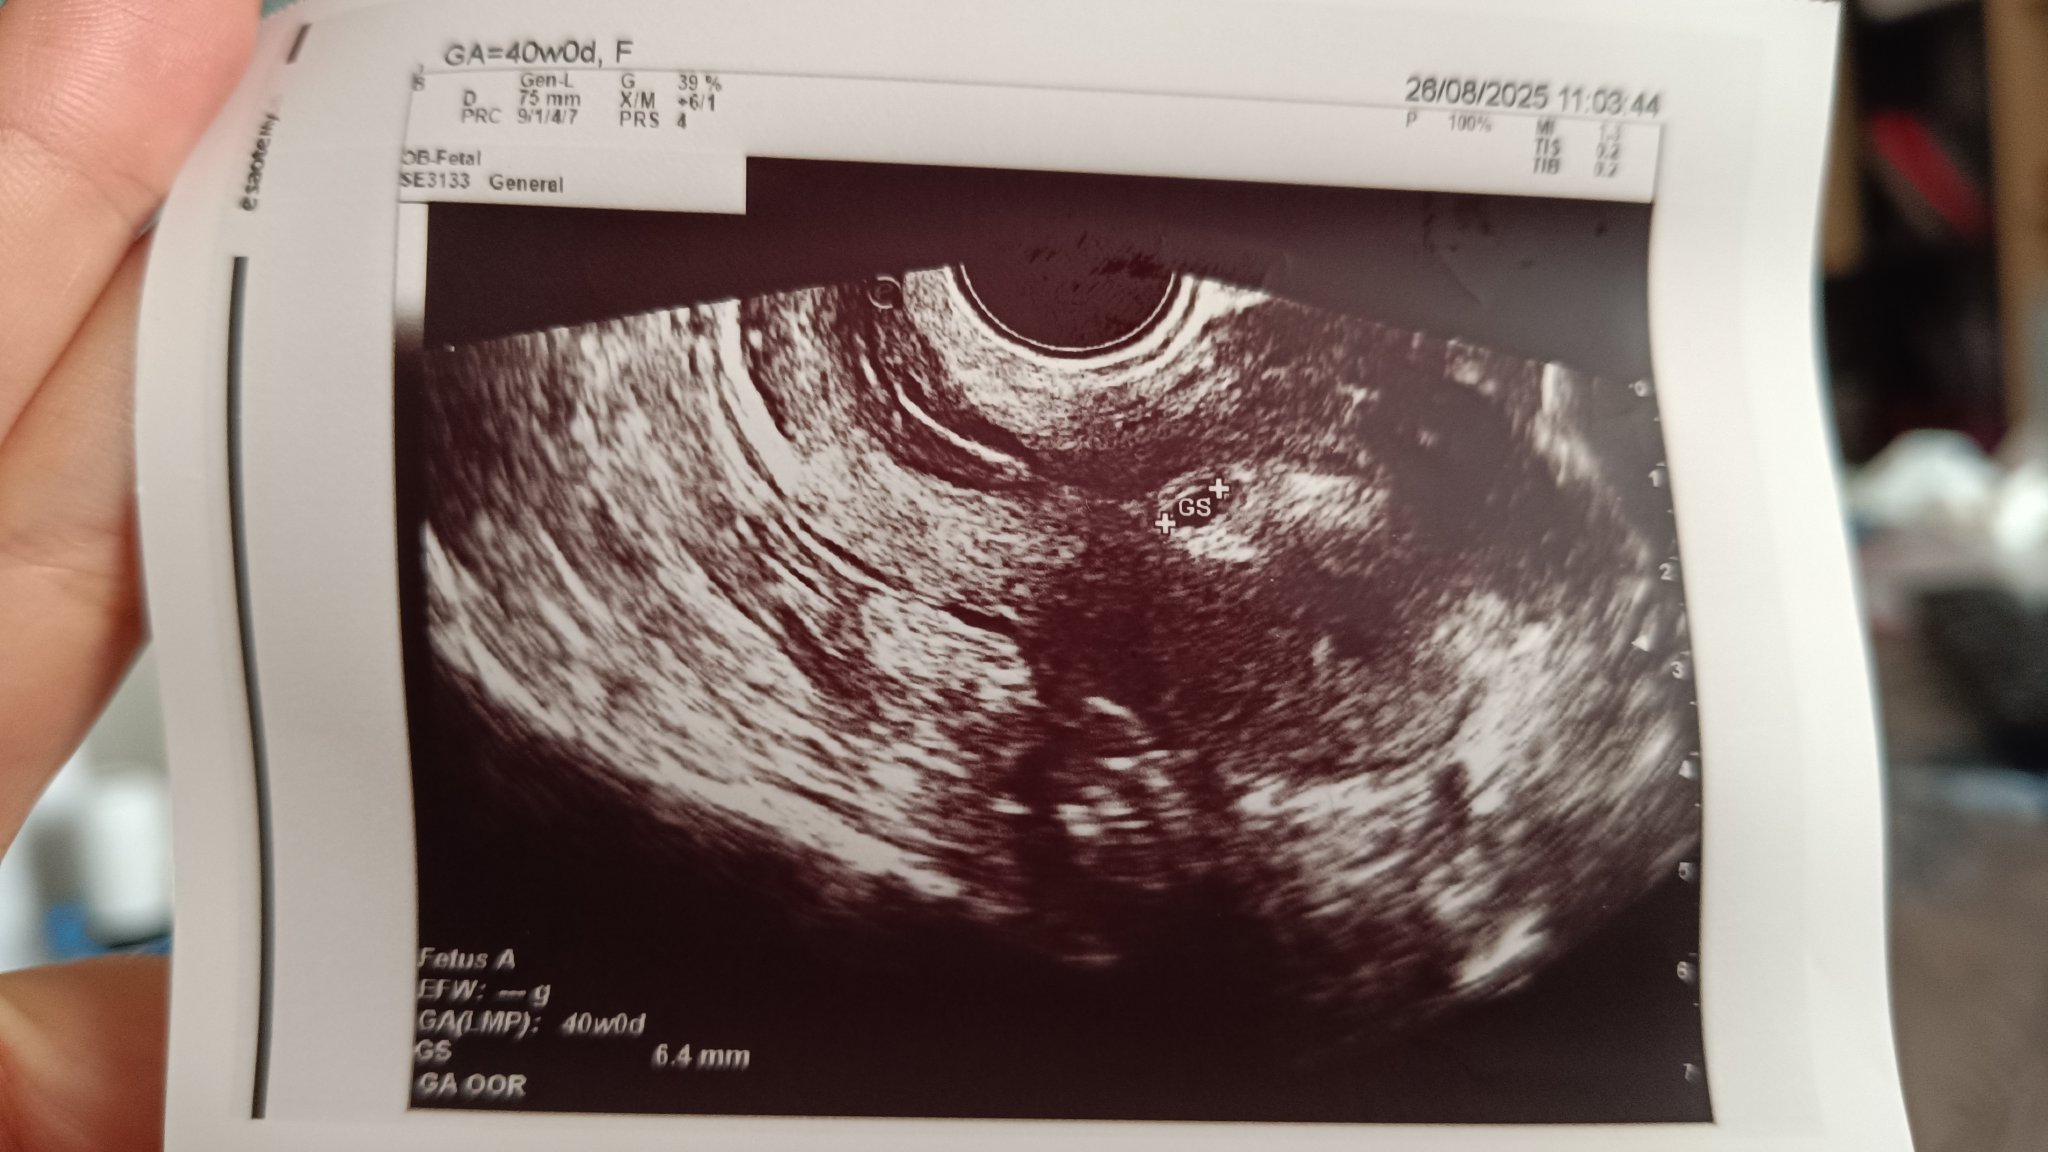

Здравейте! Преди седмица видях положителен тест (ЗЕТ) изследвах ЧХГ и се удвояваше, няколко дни по-късно получих кафеникаво зацапване. Тогава се консултирах с моя доктор и той ми изписа допълнително дуфастон 3х1 (преди това бях само на Циклогест 2х1). Зацапването спря още на следващия ден.

Днес обаче се събудих и отново имах кафеникаво зацапване. Този път отидох директно на спешен кабинет. На прегледа се видя гестационен сак с мехурче. Докторката каза, че е разположен по-ниско от колкото трябва. Трябвало да бъде в средата а при мен било ниско долу. Каза, че не се знае какъв ще бъде развоя и да чакам следващия преглед.

И още нещо на снимката пише 40w0d??? Предполагам е грешка и се има предвид 4w0d

Еми Simple Smile , тихичко честито! Ниско разположения сак най-вероятно означава, че се е имплантирал по-близо до маточната шийка. Това не винаги може да е проблем, защото с напредването на бременността и растежа на матката, често се "издърпва" нагоре. На мястото на имплантацията се образува и закрепя плацентата. Ако тя е твърде близо до шийката, по-нататък може да има риск от плацента превия (плацентата покрива частично или изцяло шийката), но на този етап е твърде рано да се правят такива прогнози. Кафеникавото зацапване пък може да е от малки кръвоизливи около мястото на имплантация и не винаги означава нещо лошо. Стискам палци точицата да се е закрепила здраво и всичко да е наред!